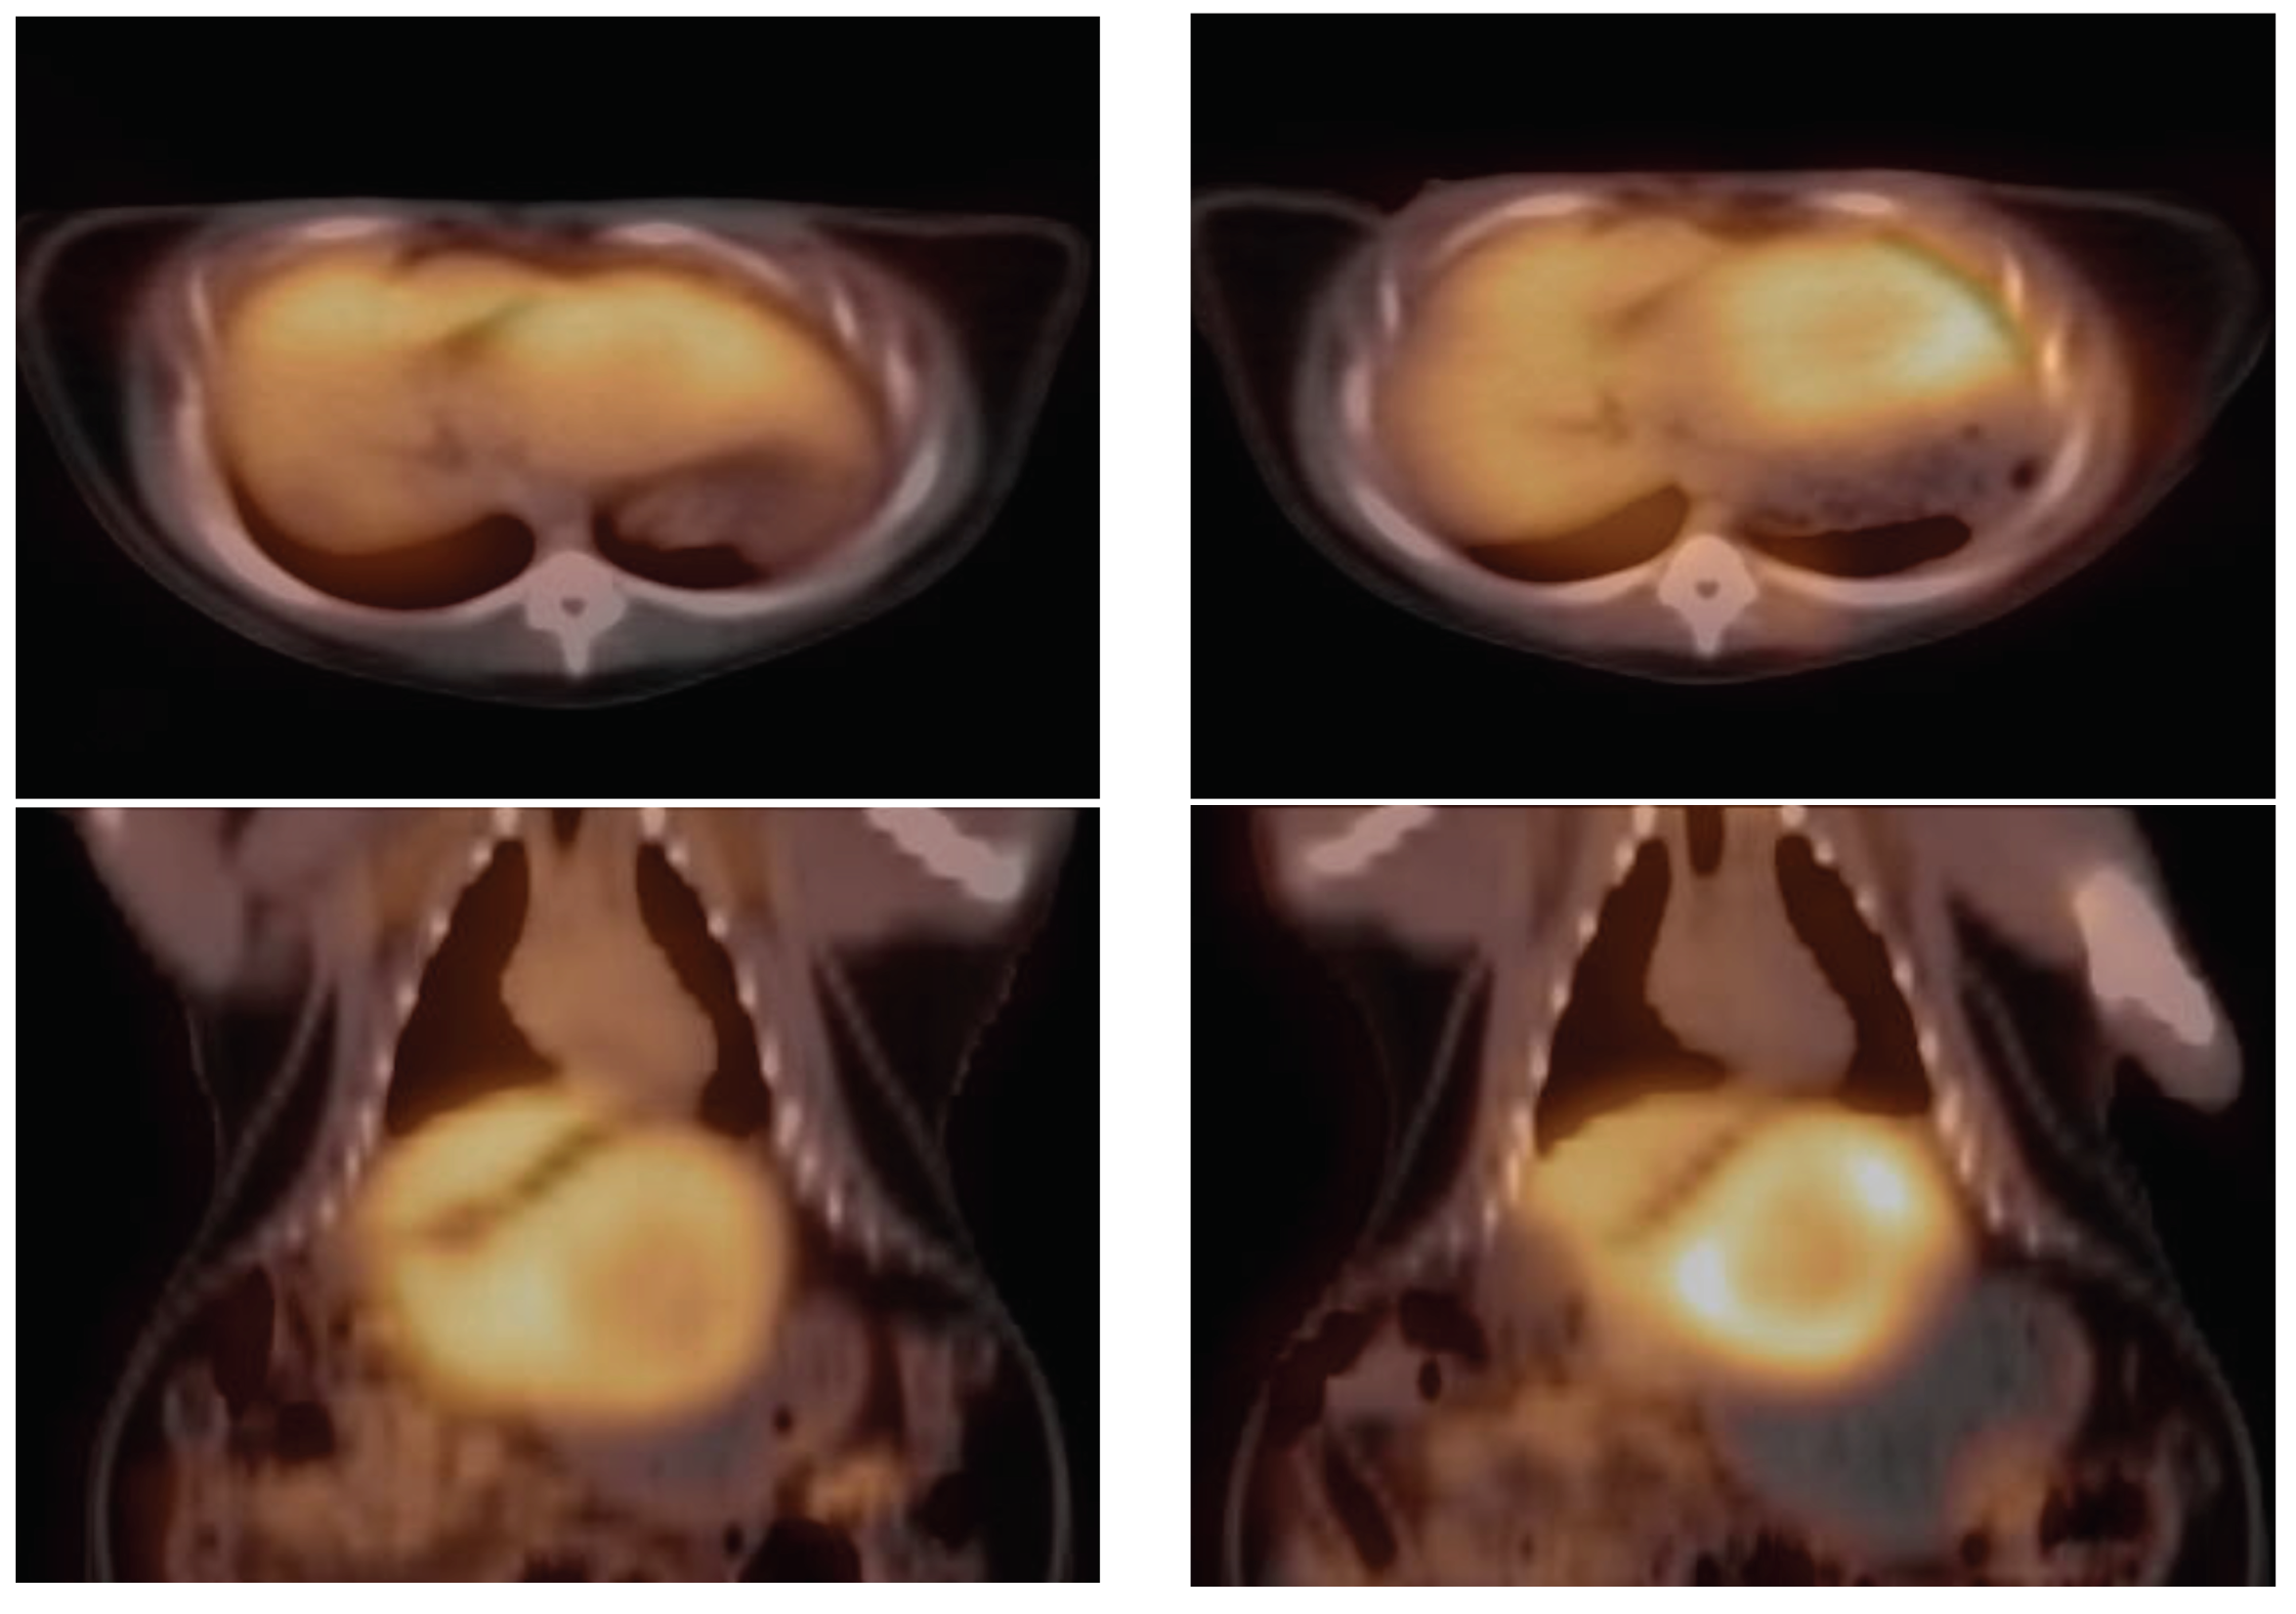

2.2. PET Imaging